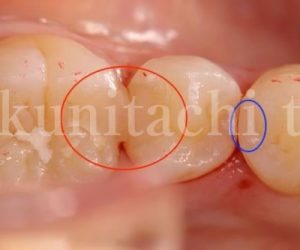

今日は「 CR(コンポジットレジン)による審美歯科治療」の症例を写真とともに見ていこうと思います。 まずは写真から見てみましょう。 患者さんは20代女性。左下の虫歯、充填物の不適合のため再治療が必要です。部位は左下の6番 […]